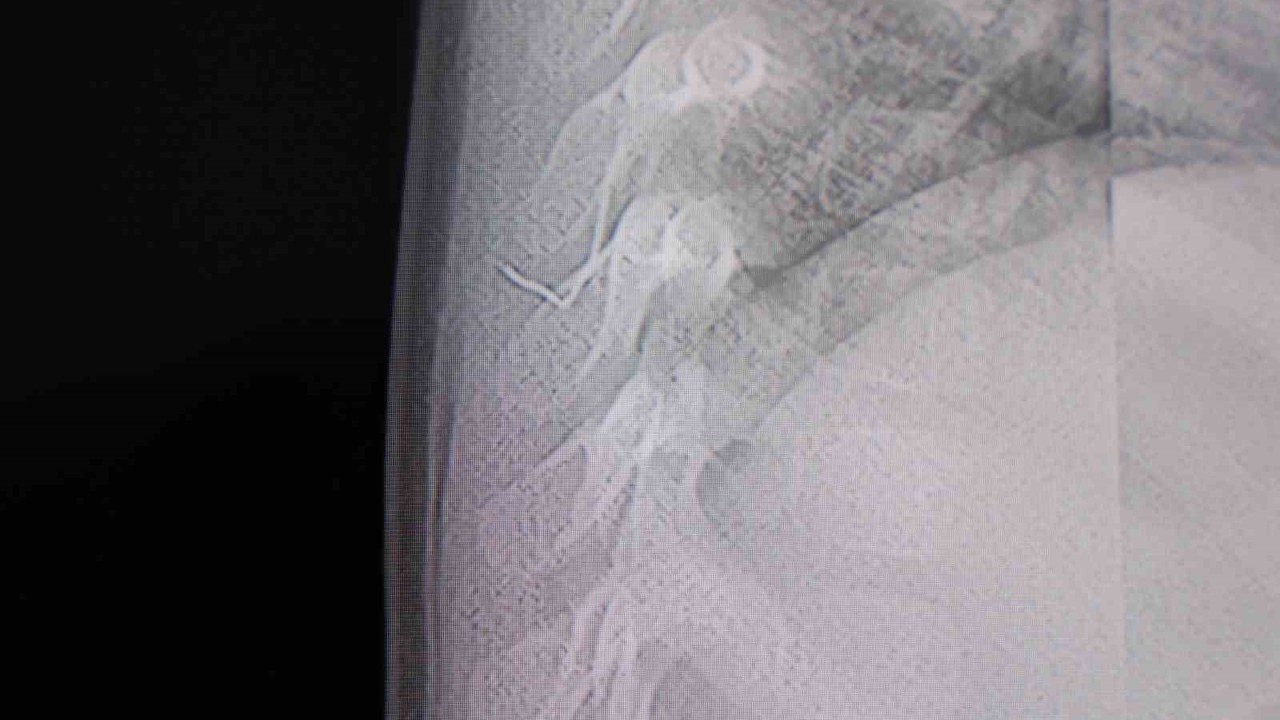

Alınan bilgiye göre, Kahramanmaraş’ta farklı ortopedi, çocuk cerrahisi ve beyin cerrahisi kliniklerine başvurusu yapılan bir yaşındaki bebeğin, sırt bölgesinde yabancı bir cisim olduğu ancak müdahalenin zor olduğu ve 8 yaşına kadar beklenmesi gerektiği bildirildi. Aile, bebekleri için son olarak HG Hospital’e başvurdu. HG Hospital Beyin ve Sinir Cerrahisi Uzmanı Prof. Dr. İdris Altun tarafından yapılan tetkiklerde, yabancı cismin cilt altında, omurilik kanalına yakın bir bölgede olduğu ve akciğer zarına doğru ilerlediği belirlendi. Hasta, genel anesteziye alınmadan, lokal anestezi ve sedasyon eşliğinde ameliyata alındı. Yapılan müdahalede yabancı cisim tamamen çıkarıldı. Çıkarılan cismin, ince zımba teline benzer metal bir tel olduğu ve yaklaşık 2 santimetre uzunluğunda bulunduğu tespit edildi. Hasta, aynı gün taburcu edildi.

Konuya ilişkin açıklama yapan Prof. Dr. İdris Altun, "Sırtında yabancı bir cisim olduğu söylenmiş ancak çıkarılamayacağı ve 8 yaşına kadar beklenmesi gerektiği ifade edilmişti. Bize başvurduğunda yaptığımız tetkiklerde, cilt altında, omurilik kanalına çok yakın ve akciğer zarına doğru ilerleyen bir yabancı cisim tespit ettik. Hastamızı tamamen uyutmadan, lokal anestezi ve sedasyon eşliğinde müdahale ederek lezyonu tamamen çıkardık. Çıkardığımız cismin ince zımba teline benzer, yaklaşık 2 santimetre uzunluğunda metal bir tel olduğunu gördük. Bu yabancı cisim alınmasaydı, bölgede enfeksiyon gelişebilirdi. Enfeksiyon sonucu omurilik kanalında ciddi hasarlar oluşabilir, çocuk büyüdükçe cismin hareket etmesine bağlı olarak omurilikte zedelenmeler meydana gelebilirdi. Ayrıca yana doğru ilerleyerek akciğer zarına ve akciğere batma riski vardı. Bu da enfeksiyona ve ilerleyen süreçte tümörle karışabilecek tablolara neden olabilirdi. Şu an hastamız gayet sağlıklı. Gerekli kontrolleri yaptık ve aynı gün taburcu ettik" dedi.